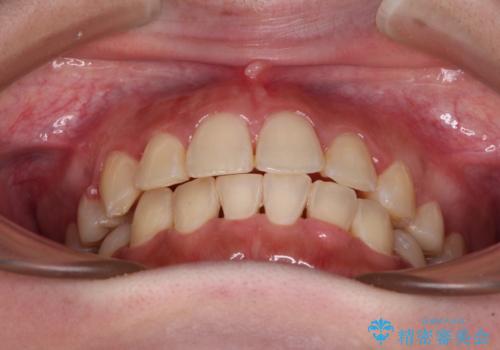

- 八重歯やデコボコをインビザラインで治療したいとのことで来院された患者様です。

インビザライン単体で治療を行うには叢生が強いと判断されたため、事前にワイヤー装置で抜歯矯正を行い、ある程度改善してからインビザラインにて仕上げていくこととしました。